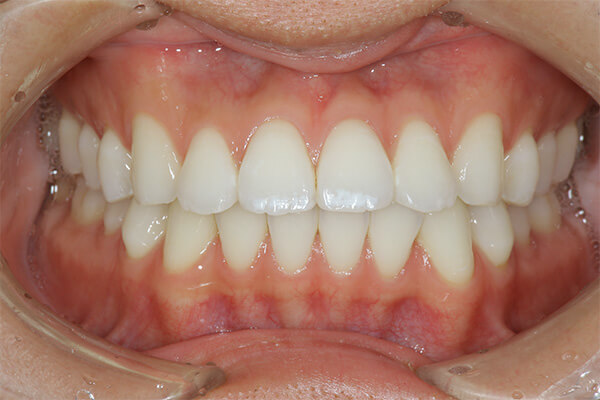

事故により上の前歯がなくなってしまいました。そのままインプラントをするのではなく、矯正治療により歯並びの改善をすることが、インプラントの予後を改善するポイントです。噛み合わせが悪いままインプラントをするとインプラントが後々トラブルを起こすことがあります。

インビザラインによる矯正治療後にインプラント治療を行い、治療終了。先天欠損であった右下の前歯は接着ブリッジによる治療を行いました。

抜歯に伴う骨欠損が大きい場合は、大規模な骨増生が必要になることがあります。

1年半

326万円(税込)